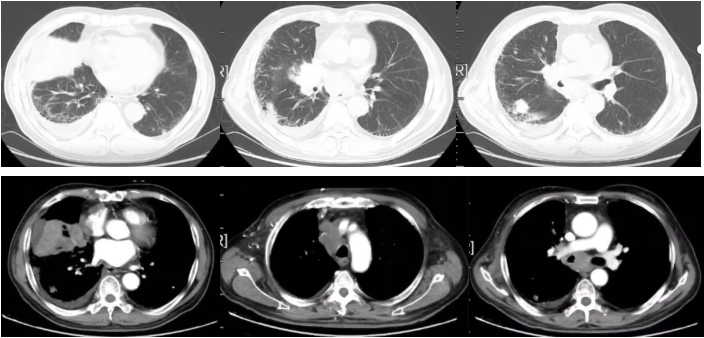

图2

疗效评价:PD。

图3

2022-09-17胸部平扫CT:恶性肿瘤维持性化学治疗后,较2022-7-20胸部CT旧片,右肺中叶占位(7.3×4.4cm)缩小;双肺部分结节增大;纵隔及右肺门淋巴结缩小;主动脉左侧旁(2-22)淋巴结稍增大:右侧胸腔积液增多;左侧新增胸腔积液;胸壁水肿增厚,双侧腋窝小淋巴结,请结合临床;余未见显著变化。附见,胰尾较前稍增粗:肝S4段新增低密度小结节,请结合腹部相关检查。

疗效评价:SD。

2022-11-16胸部平扫CT:恶性肿瘤维持性化学治疗后,较2022-9-16日胸部CT,右肺中叶占位(2.2×1.9cm)缩小;双肺大部分结节消失;右侧胸腔积液减少,左侧胸腔积液消失;纵膈及双侧腋窝淋巴结缩小;扫描层面内肝脏结节本次未见明确显示,胰腺结节缩小;余较前变化不大。

疗效评价:PR。